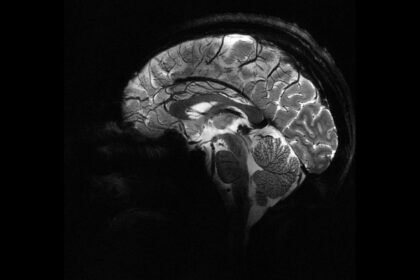

Epilepsiye farklı nedenler yol açsa da, vakaların yaklaşık yüzde 30’u beyindeki yapısal anormalliklerden kaynaklanıyor. Ancak bu lezyonlar, özellikle de beynin kıvrımlarının derinliklerinde sakl...